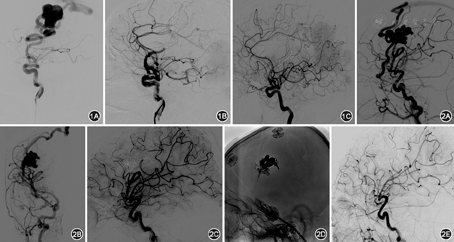

16例均行血管内栓塞治疗,其中使用弹簧圈辅助Onyx胶栓塞10例,单纯使用弹簧圈栓塞6例。术中均采用全麻,全身肝素化,微导丝辅助Echelon10/14微导管到达瘘口处,超选造影了解瘘口血流、大小等情况,调整微导管位置,位置满意后植入弹簧圈。若血流较快,微导丝辅助另一Echelon14微导管至瘘口,从两微导管轮流植入弹簧圈。植入弹簧圈直至瘘口闭塞(图1),或者弹簧圈填塞,瘘口血流减慢后,再经Echelon14微导管植入Onyx18或者Onyx34,闭塞瘘口及引流静脉近端(图2)。2例患者合并2个瘘,行分期栓塞。术后严格控制血压,低于基础血压的10~20 mmHg(1 mmHg=0.133 kPa)。高流量瘘完全栓塞者,适当低分子肝素抗凝1~3 d,术前有癫痫的继续抗癫痫对症治疗,有头痛加重和癫痫发作者,积极复查头颅CT,排除颅内出血。

脑动静脉瘘因无畸形血管团,为动静脉之间的直接沟通,瘘口处动静脉间落压差较小,栓塞瘘口后供血动脉内压力会骤然升高,加上脑动静脉瘘邻近的正常脑组织因盗血呈缺血状态,脑血管短期内自动调节功能不良,容易发生正常灌注压突破。因此术中及术后应控制性降压,有人主张将血压控制在基础血压的2/3左右[2],我们认为,因脑动静脉瘘的患者多为年轻患者或者儿童,基础血压不高,我们认为,将血压控制在低于基础血压10~20 mmHg的基础上,可以有效预防再灌注出血,还能避免其他组织的低灌注。本组16例患者均严格控制血压和术后液体入量,无出血并发症。其次,脑动静脉瘘栓塞术后,可导致引流静脉血流减慢导致急性血栓形成,因引流静脉多引流正常脑组织的血流,故急性静脉血栓形成可导致静脉性梗死和出血[11,12],也有报道形成继发性脑积水[11]。本组6例高流量患者,引流静脉异常粗大迂曲,伴有瘤样扩张(图1A),术中完全栓塞瘘口,术后复查CT无出血,在有效控制血压的基础上,术中肝素抗凝,术后给予低分子肝素抗凝1~3 d,预防引流静脉急性血栓形成,安全渡过危险期,也有作者建议给予2 d~2周[11]。此外,栓塞术后可出现血流动力学改变,诱发癫痫或使术前癫痫症状加重,故术前合并癫痫的患者术后更需加强抗癫痫治疗,癫痫发作者,必须警惕出血,需急诊复查头颅CT。术后患者多有头痛,或者在原有的基础上加重,必须警惕颅内出血,积极复查头颅CT,术后头痛多因血流动力学改变所致,经对症治疗1~2周后多能缓解。